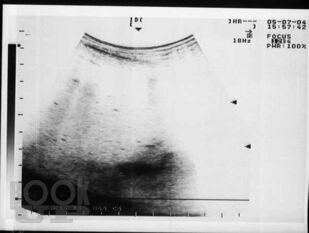

Материалом послужили данные многолетнего обследования больных декомпенсированным циррозом печени, проанализированы клинические проявления спонтанного бактериального перитонита, в том числе системной воспалительной реакции, использован широкий комплекс современных методов: подсчет полиморфноядерных нейтрофилов в асцитической жидкости, микробиологическое исследование крови и асцита, ультразвуковая оценка акустической однородности асцита, исследовано содержание цитокинов, С-реактивного белка, количественный и качественный состав химических компонентов – маркеров потенциальных возбудителей инфекции асцитической жидкости методом газовой хроматографии-масс-спектрометрии. В работе представлены результаты исследования позволяющие диагностировать спонтанный бактериальный перитонит на более ранних сроках, что позволяет проводить своевременную адекватную терапию. Рассмотрены вопросы дифференциальной диагностики первичного и вторичного бактериального перитонита, приведены яркие клинические примеры, отражающие трудности диагностики.

В книге на основе анализа литературы и собственных данных автором представлены современные аспекты этиологии, патогенеза, диагностики, профилактики и лечения спонтанного бактериального перитонита у больных циррозом печени. Материалом послужили данные многолетнего обследования больных декомпенсированным циррозом печени, проанализированы клинические проявления спонтанного бактериального перитонита, в том числе системной воспалительной реакции, использован широкий комплекс современных методов: подсчет полиморфноядерных нейтрофилов в асцитической жидкости, микробиологическое исследование крови и асцита, ультразвуковая оценка акустической однородности асцита, исследовано содержание цитокинов, С-реактивного белка, количественный и качественный состав химических компонентов – маркеров потенциальных возбудителей инфекции асцитической жидкости методом газовой хроматографии-масс-спектрометрии.